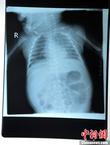

8月23日,黑龙江被“缝衣针”扎伤女婴在哈尔滨医科大学附属第一医院进行手术,成功取出三根长达4.5厘米的缝衣针,目前患儿正在术后观察中,尚未脱离危险期。8月19日黑龙江省北安市赵光镇一名出生仅两个月的女婴两度被“缝衣针”扎伤病情危重。图为婴儿正在被推进手术室。(哈尔滨医大一院供图)中新社发